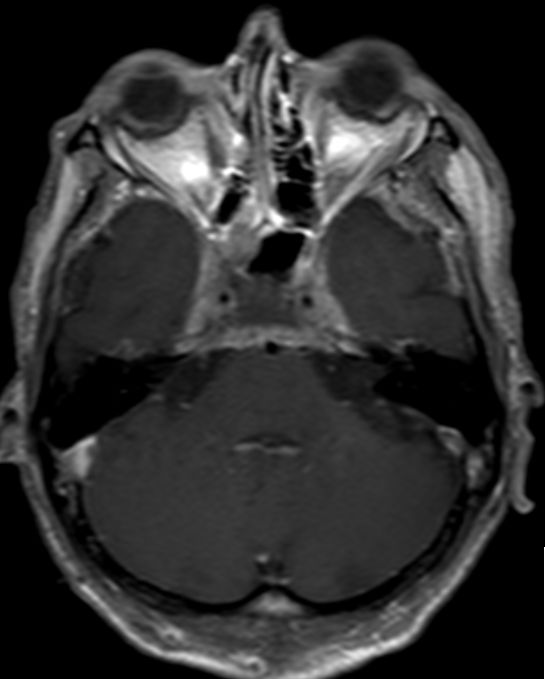

55-jähriger Mann, der vor 6 Monaten wegen eines Oropharynxkarzinoms links pT3 pN0 M0, L1, V0, Pn1 radikal operiert wurde und eine postoperative Radiochemotherapie mit Cisplatin erhielt. Jetzt Schädelbasis-Metastase im Bereich des Sinus cavernosus. Klinisch Hirnnervenausfälle links N. abducens, rechts N. opticus, - trochlearis, - trigeminus 1. Ast, unsicheres Gangbild, Störung des Schluckaktes. | ||